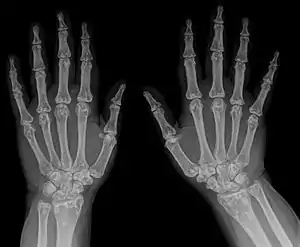

| Osteopoikilosis on an X-ray of the hands | |

Osteopoikilosis is a benign, autosomal dominant sclerosing dysplasia of bone characterized by the presence of numerous bone islands in the skeleton.[1]

In terms of the diagnosis Osteopoikilosis is radiographically evaluated via the presence of multiple symmetrical circular sclerotic opacities [2]

The radiographic appearance of osteopoikilosis on an X-ray is characterized by a pattern of numerous white densities of similar size spread throughout all the bones. This is a systemic condition. It must be differentiated from blastic metastasis, which can also present radiographically as white densities interspersed throughout bone. Blastic metastasis tends to present with larger and more irregular densities in less of a uniform pattern. Another differentiating factor is age, with blastic metastasis mostly affecting older people, and osteopoikilosis being found in people 20 years of age and younger.

The distribution is variable, though it does not tend to affect the ribs, spine, or skull.[3]